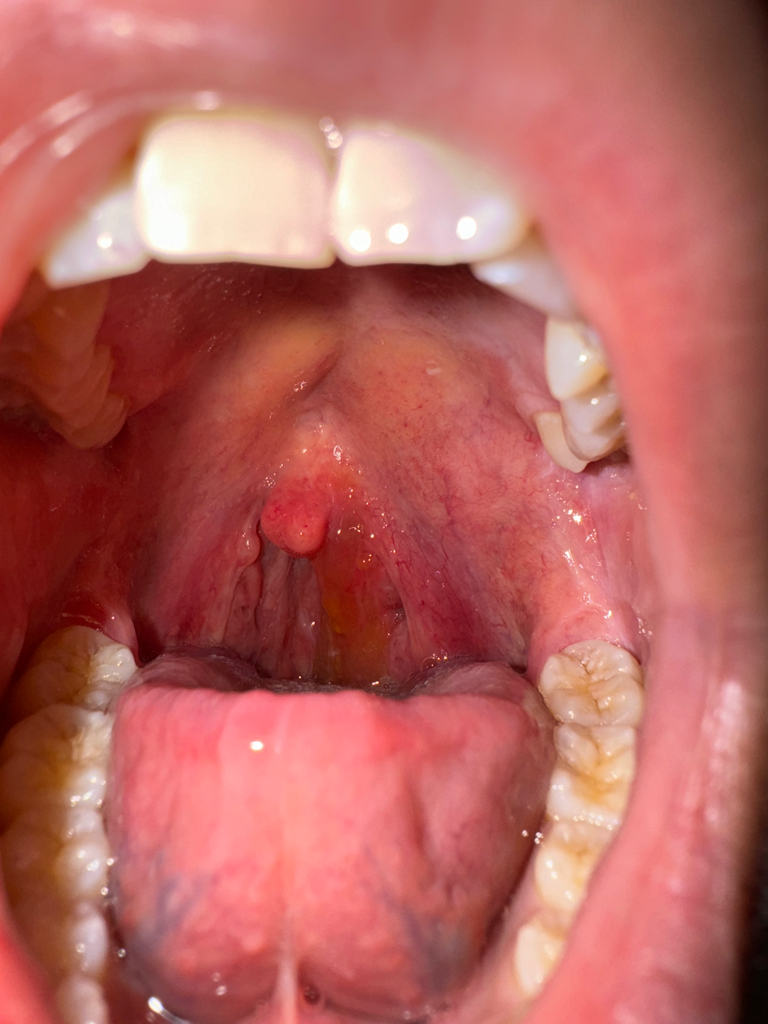

다음은 입 사진입니다.. 혐오스러우니 조심해주세요.

사진에 관찰되는 모습으로는 편도염보다 인두염이 문제가 되는 상황입니다. 편도는 정상적이고 염증이 없는 모습인 반면 인두에는 염증이 심합니다. 이비인후과를 방문해보시면 되겠습니다.

올려주신 사진은 편도가 잘 보이지 않습니다.